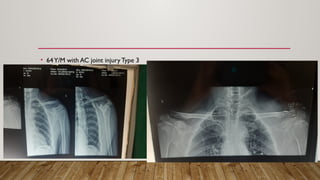

CASE

• 30 yrs/ F with history of fall from scotter

• 64Y/M with AC joint injury Type 3